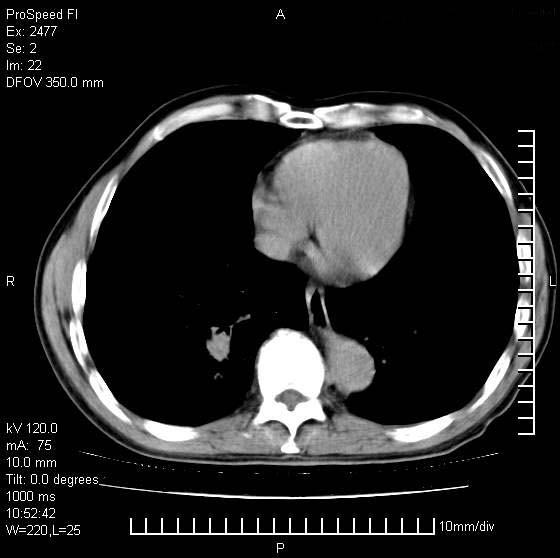

以下是引用天南地北在2007-10-9 14:29:00的发言:[br]1:右上肺结核[br]2:右肺下叶肿块:不支持肺癌,首先考虑炎性病变-肺脓疡可能性大[br]理由:1:临床病史支持,肺脓肿症状不明显应该是不规则服药造成。[br] 2:肿块边缘模糊,周围可见炎性渗出,长毛刺,内见支气管征,不过有点不规则。[br] 我感觉下肺癌这个诊断有点偏左,建议积极抗炎治疗后复查

以下是引用卜一在2007-10-9 15:55:00的发言:[br][br] [br] 1:右上肺结核[br]2:右肺下叶肿块:不支持肺癌,首先考虑炎性病变-肺脓疡可能性大[br]理由:1:临床病史支持,肺脓肿症状不明显应该是不规则服药造成。[br] 2:肿块边缘模糊,周围可见炎性渗出,长毛刺,内见空气支气管征,不过有点不规则。[br] 我感觉下肺癌这个诊断有点偏左,建议积极抗炎治疗后复查![br]支持! [br] [br] [br]

以下是引用wxy7406在2007-10-9 21:02:00的发言:[br]结合临床病史首先考虑感染性病变,但周围型肺癌不能除外,1.患者年龄偏大2.临床有咯血3.(也觉得是最重要的一点)病灶内有偏心性空洞。

以下是引用王仕学在2007-10-9 13:48:00的发言:[br]右下肺周围性肺癌可能性大,最好活检吧

以下是引用hhcckk在2007-10-9 15:18:00的发言:[br]右上肺病灶考虑结核,病灶多种形态并存(纤维化、增殖性病灶并存)[br]右下肺病灶比较难说,个人意见更趋向于“天南地北”的诊断----肺脓肿[br]1、病人有明显的寒战,高热,肿瘤病人很少出现[br]2、病灶周围的肺纹理走向柔和,没有肿瘤病灶常见的集束征[br]3、病灶边缘的毛刺较长,恶性肿瘤多为短毛刺[br]痰中血丝和病人的年龄是两个不利于良性肿块的因素,建议早点活检

以下是引用ydx_74在2007-10-9 15:53:00的发言:[br]右上肺结核,右下中心性肺癌可能大,肺门淋巴结肿大。